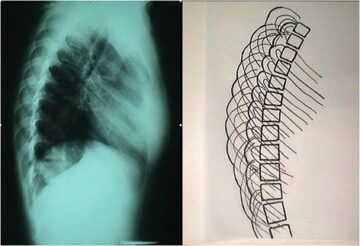

اكتشاف العمود الفقري: فهم التشريح وتأثيره على اعوجاج العمود الفقري فهم العمود الفقري وأجزائه يُعد خطوة مهمة لكل من المرضى والأهالي، خصوصًا عند تشخيص اعوجاج العمود الفقري (Scoliosis). هذا الانحناء الجانبي غير الطبيعي للفقرات

متى يحتاج طفلك إلى أشعة لتشخيص اعوجاج العمود الفقري؟ دليل مبسط للأهل يعاني العديد من الأطفال والمراهقين من اعوجاج العمود الفقري، وهو حالة يتميز بها العمود الفقري بالانحناء الجانبي غير الطبيعي. في كثير من